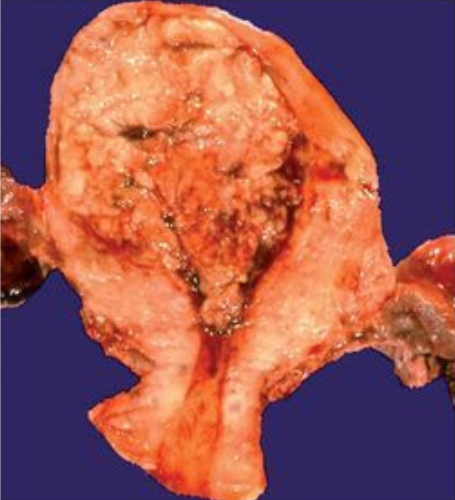

Cáncer epitelial de ovario